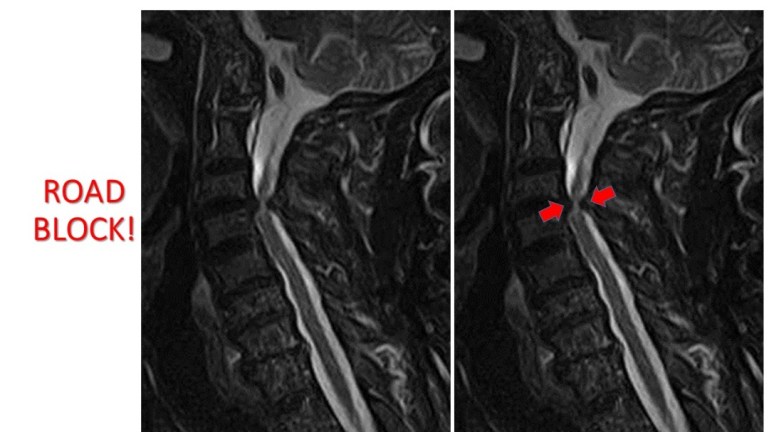

This is like someone being sent on an errand and getting stuck in traffic due to a road block. Similar to one of our Police checkpoints. As you know, this could lead to serious traffic jam and a long tailback. The message therefore arrives late, if at all. You know as well that the message can only arrive if the checkpoint is cleared or removed. Then, the traffic will flow easily and the errand can be delivered.

The MRI scan revealed an obstruction in the neck in my chap. The bones in the neck had worn away the shock absorber and this was now causing pressure on the spinal cord. This is the reason for the weakness in the arms and legs. It is also the cause of the numbness which he describes as ‘cold as ice’.

An urgent operation was required. We needed to clear away the police checkpoint and remove the obstruction. This would relieve the pressure on the spinal cord so it can wake up and continue doing its job of moving the arms, legs, and enabling us to urinate easily. Pressure on the spinal cord can cause all sorts of problems. Some people have sharp lancinating pains, shock-like sensations and wicked feelings of ants crawling all over the body. Weird and horrible sensations of heat in the body like one is being fried with pepper like kilishi can also happen.